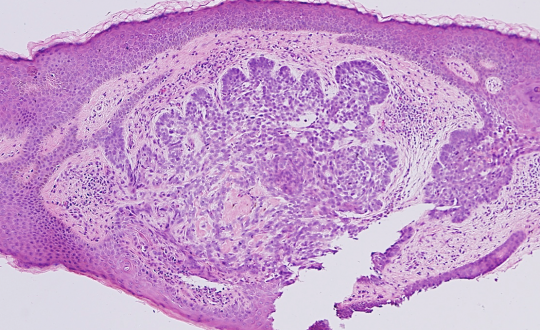

VA33: Superior Nasal Ala, Basal Cell Carcinoma, Nodular

- * indicate areas of necrotic cells not yet undergone liquifactive necrosis